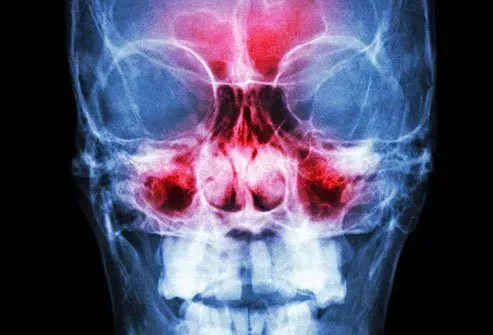

Vos sinus sont enflés

Un simple rhume peut enflammer les zones creuses derrière vos pommettes et votre front. Le gonflement pourrait provoquer des douleurs qui s'aggravent lorsque vous vous penchez. Il peut être difficile de respirer car le mucus qui peut devenir épais et jaune ou vert ne s'écoule pas correctement. Les médicaments en vente libre peuvent souvent vous aider à le gérer. Il n'est pas nécessaire d'appeler votre médecin à moins que les symptômes ne soient mauvais, ne disparaissez pas ou ne deviennent pas empirés.